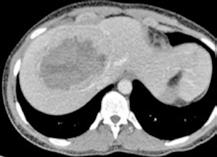

Se solicita una Ecografía abdominal donde se visualiza una masa hepática de aproximadamente 12 cm y directamente se solicita una Tomografía Computarizada (TC) urgente. Se confirma la masa hepática, que mide 13x11x10 cm, con signos de sangrado reciente pero sin sangrado activo.

Localizada en los segmentos VII, V y parte del IV, entre las venas suprahepáticas (VSH) derecha y media, contactando con ellas en su origen. Caudalmente llega hasta la bifurcación hiliar, cercano a la bifurcación portal. Esta masa presenta una captación periférica en fase arterial y algo más isodensa en fase venosa y tardía, con un área central heterogénea e hipodensa en estas últimas fases. Con este comportamiento radiológico, se establece un diagnóstico de sospecha de hepatocarcinoma fibrolamelar o adenoma. Como variante anatómica, se objetiva una arteria hepática que nace de la arteria mesentérica superior (Figura 1). El paciente es ingresado en Digestivo para estudiar la lesión. Se realiza una Resonancia Magnética (RM) y se establece un diagnóstico de sospecha de hepatocarcinoma fibrolamelar (Figura 2). Se descartó una biopsia por el riesgo de resangrado que presentaba. La alfafeto proteína solicitada durante el ingreso fue normal. Dado que se trata de una lesión hepática sintomática y que ha presentado un sangrado, está indicada la resección de la lesión, pero su tamaño y localización lo impiden. La lesión está tan cerca de las VSH que resulta imposible disecarlas y seccionarlas con seguridad, siendo imposible la cirugía. Se comenta el caso en el comité multidisciplinar y se decide embolizar la tumoración con el objetivo de evitar un nuevo sangrado y disminuir su tamaño para separarla de las estructuras vasculares. Se cateteriza la arteria hepática, desde la mesentérica superior. Se emboliza con micropartículas

Figura 1 (A, B y C).

Imágenes de TC: Gran masa hepática localizada en segmentos VII, V y parte del IV. Signos de sangrado no activo.

A)Masa localizada entre VSH media y derecha.

B) Masa en contacto con rama portal.

C) Imagen en 3D donde se ve la gran masa y su relación con el resto del hígado.